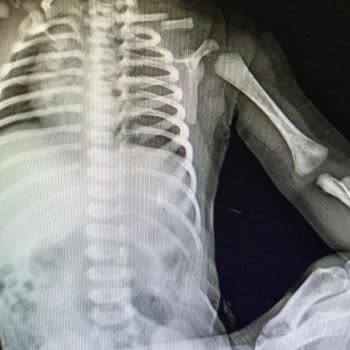

Oğlum gece 1'de hastalandı ve biz de özel İstanbul Hospital Hastanesi'ni arayarak çocuk doktoru olup olmadığını sorduk. Nöbetçi var denildi, gittik. Muayene ücreti 1500 TL verdik, muayenemiz oldu. Doktor serum, iğne, hava röntgen ve influenza testi istedi. Eşime, veznedeki hiçbir aydınlatma yapılmad...